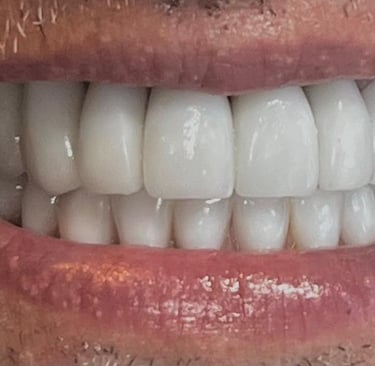

Aspecto Clínico Final - Fotografias originais — nenhuma contém retoques — A cor dos dentes é escolhida de acordo com o gosto e a preferência estética de cada paciente.

Depois

Depois - Restauração em resina associada ao clareamento dental.